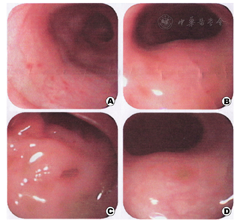

例1 男,3 d,生后面色发绀、气促、哭吵不安,在生产医院治疗无效于2012年10月入本院。患儿系G8P2孕38+3周剖宫产,羊水胎粪污染,脐带绕颈1周,出生体重3 kg,Apgar评分:1~8分,5~9分。其母38岁,人工流产3次,自然流产3次,否认此次孕期感染史。入院体查:体温37.5 ℃,呼吸62次/min,脉搏140次/min,体重2.95 kg。足月儿貌,稍易激惹,哭声响亮,皮肤无黄染,前囟平软,双肺呼吸音粗,可闻及少许湿罗音,心腹无异常,四肢肌张力可,原始反射引出不完全。辅助检查,血常规:白细胞24.6×109/L,中性比值0.716,血红蛋白182 g/L;血气分析示Ⅰ型呼衰;胸片示肺炎;CRP 19.2 mg/L;ESR 11 mm/h。入院诊断:新生儿重症肺炎并Ⅰ型呼吸功能衰竭,新生儿败血症。后经腰穿脑脊液检查排除"化脓性脑膜炎"。入院后予抗感染及对症支持治疗,患儿病情一度好转,复查血常规及CRP均正常。入院第18天病情反复,出现发热,体温最高达39 ℃,拒奶,哭闹,无明显呼吸道症状,病情进行性加重,于第21天解黄稀水样便,10+次/d,伴血及黏液。调整抗生素(最强时为万古霉素与亚胺培南、氟康唑、甲硝唑联合应用),静脉用丙种球蛋白(2.5 g×5 d),维持水电解质平衡,改腹泻奶和减量喂养至完全禁食等综合治疗,病情仍进行性加重,并出现腹胀,肠鸣音减弱。第2次复查脑脊液正常,胸片示肺炎好转,腹部立位片未见特异性改变。但血常规示白细胞进行性升高,最高达126.8×109/L;多次大便常规见红细胞和白细胞,黏液、潜血阳性,轮状病毒抗原阴性,大便培养阴性;骨髓片示骨髓增生明显活跃,粒系增生明显活跃,红系增生明显减低,血片中可见幼粒细胞,可见中毒颗粒。体液免疫发现IgE↑(412.10 KIU/L),补体C3、C4↓,余正常;食物过敏原筛查阴性;行结肠镜检查发现横结肠以下黏膜充血水肿,点片状糜烂,并发现数个溃疡,最大为0.5 cm×0.5 cm(图2);送两处病理活检:黏膜明显水肿、血管扩张充血、部分黏膜坏死脱落伴有较多炎症细胞浸润,以淋巴细胞为主,结合临床符合黏膜慢性炎症伴有溃疡形成(图1、图2)。于第49天考虑"炎症性肠病"加用糖皮质激素[甲泼尼龙2 mg/(kg·次)],停万古霉素,微量母乳喂养(3 ml/次)。随后病情迅速好转,外周血白细胞、CRP逐渐下降,大便次数及性状好转。甲泼尼龙逐步减量于第59天(用药第10天)改为泼尼松2 mg/kg分3次口服,第61天带药出院,随访指导激素逐步减量至用药30 d停药。继续随访至今,生长发育、大便情况均良好。